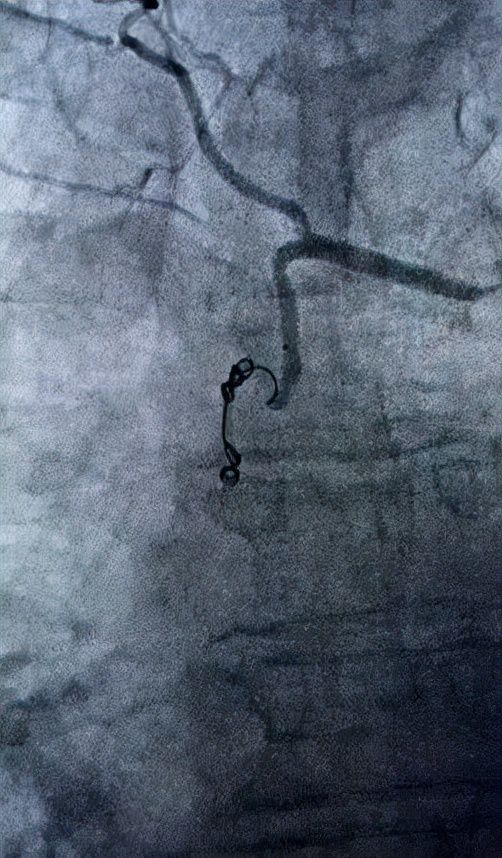

在积极完善术前准备后,清华大学附属垂杨柳医院血管外科对患者进行了 肺动脉造影、选择性支气管动脉造影、选择性支气管动脉栓塞术 。

术中发现支气管动脉参与肿瘤供血,透视下将导管选入粗大迂曲的病变支气管动脉。

就在缓慢推注栓塞剂的时候,意外情况发生了,患者突发咳血加重,血氧饱和度低至70%,导管室护士在床边不断地抽吸病人咯出的血液,医生继续透视下推注栓塞剂,支气管动脉血流缓慢的被阻断了,病人咯血也很快就停止了。